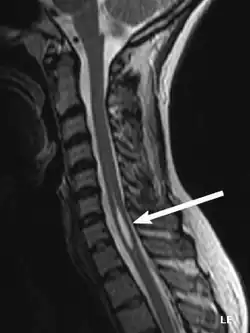

Physicians now use magnetic resonance imaging (MRI) to diagnose syringomyelia. The MRI radiographer takes images of body anatomy, such as the brain and spinal cord, in vivid detail. This test will show the syrinx in the spine or any other conditions, such as the presence of a tumor. MRI is safe, painless, and informative and has greatly improved the diagnosis of syringomyelia.[18]

The possible causes are trauma, tumors, and congenital defects. It is most usually observed in the part of the spinal cord corresponding to the neck area. Symptoms are due to spinal cord damage and include pain, decreased sensation of touch, weakness, and loss of muscle tissue. The diagnosis is confirmed with a spinal CT, myelogram or MRI of the spinal cord. The cavity may be reduced by surgical decompression.[22]

Diagnostic technology is another area for continued research. MRI has enabled scientists to see the situation within the spine, including syringomyelia, before any symptoms appear. A new technology, known as dynamic MRI, allows investigators to view spinal fluid flow within the syrinx. CT scans allow physicians to see abnormalities in the brain, and other diagnostic tests have also improved greatly with the availability of new, non-toxic, contrast dyes.[36]